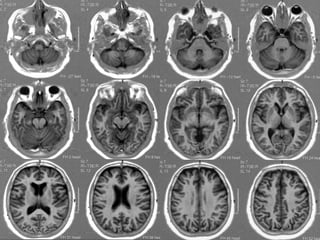

• PONTE

• PEDÚNCULO CEREBELARES MÉDIOS / CORPOS

MEDULARES        NÓDULO

VERMIS   ÚVULA

PIRÂMIDE

• CEREBELO                 FLÓCULO

HEMISFÉRIOS

SEMILUNAR

• ARTÉRIA BASILAR

• IV VENT.

• CISTERNAS PRÉ-PONTINA

CEREBELO-PONTINA

• CONDUTOS AUDITIVOS

INTERNOS

• PONTE - COLÍCULOS FACIAIS

• PEDÚNCULOS CEREBELARES MÉDIOS / CORPOS MEDULARES

• CEREBELO

VÉRMIS - NÓDULO, ÚVULA, PIRÂMIDE

• CISTERNA      HEMISFÉRIOS

PRÉ-PONTINA

• C.A.I.       CEREBELO-PONTINA

• PEDÚNCULOS CEREBELARES SUPERIORES

• CEREBELO - VERMIS (LÍNGULA, LÓBULO CENTRAL,

CULMEN, DECLIVE)

CORTE MEDIANO

• MESENCÉFALO

– TETO

– PEDÚNCULO

• BULBO (OBEX, CLAVA)

• MEDULA ESPINHAL

• VERMIS CEREBELAR (TODOS OS

LÓBULOS E FISSURAS)

• IV VENTRÍCULO - VALÉCULA

• CISTERNAS (INTERPEDUNCULAR, PRÉ

PONTINA, PRÉ BULBAR, MAGNA,

QUADRIGEMINAL)

• PEDÚNCULOS CEREBELARES

• SUPERIOR

• INFERIOR

• HEMISFÉRIOS CEREBELARES

• LÓBULOS QUADRANGULAR, SEMILUNAR, AMÍGDALAS

• PEDÚNCULO CEREBELAR MÉDIO

• HEMISFÉRIO CEREBELAR

•   HEMISFÉRIOS CEREBELARES (LÓBULOS QUADRANGULAR,

SEMILUNAR, BIVENTRE, CORPO MEDULAR)